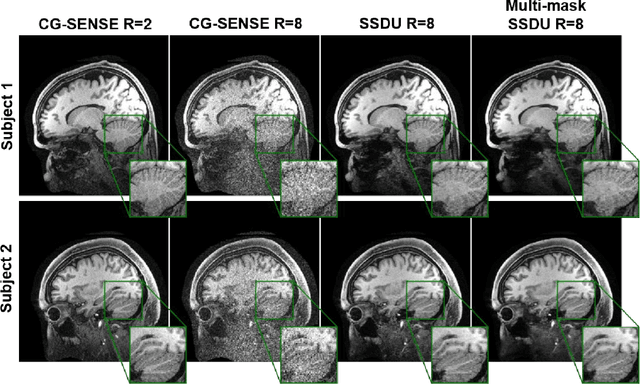

Abstract:Purpose: To develop an improved self-supervised learning strategy that efficiently uses the acquired data for training a physics-guided reconstruction network without a database of fully-sampled data. Methods: Currently self-supervised learning for physics-guided reconstruction networks splits acquired undersampled data into two disjoint sets, where one is used for data consistency (DC) in the unrolled network and the other to define the training loss. The proposed multi-mask self-supervised learning via data undersampling (SSDU) splits acquired measurements into multiple pairs of disjoint sets for each training sample, while using one of these sets for DC units and the other for defining loss, thereby more efficiently using the undersampled data. Multi-mask SSDU is applied on fully-sampled 3D knee and prospectively undersampled 3D brain MRI datasets, which are retrospectively subsampled to acceleration rate (R)=8, and compared to CG-SENSE and single-mask SSDU DL-MRI, as well as supervised DL-MRI when fully-sampled data is available. Results: Results on knee MRI show that the proposed multi-mask SSDU outperforms SSDU and performs closely with supervised DL-MRI, while significantly outperforming CG-SENSE. A clinical reader study further ranks the multi-mask SSDU higher than supervised DL-MRI in terms of SNR and aliasing artifacts. Results on brain MRI show that multi-mask SSDU achieves better reconstruction quality compared to SSDU and CG-SENSE. Reader study demonstrates that multi-mask SSDU at R=8 significantly improves reconstruction compared to single-mask SSDU at R=8, as well as CG-SENSE at R=2. Conclusion: The proposed multi-mask SSDU approach enables improved training of physics-guided neural networks without fully-sampled data, by enabling efficient use of the undersampled data with multiple masks.